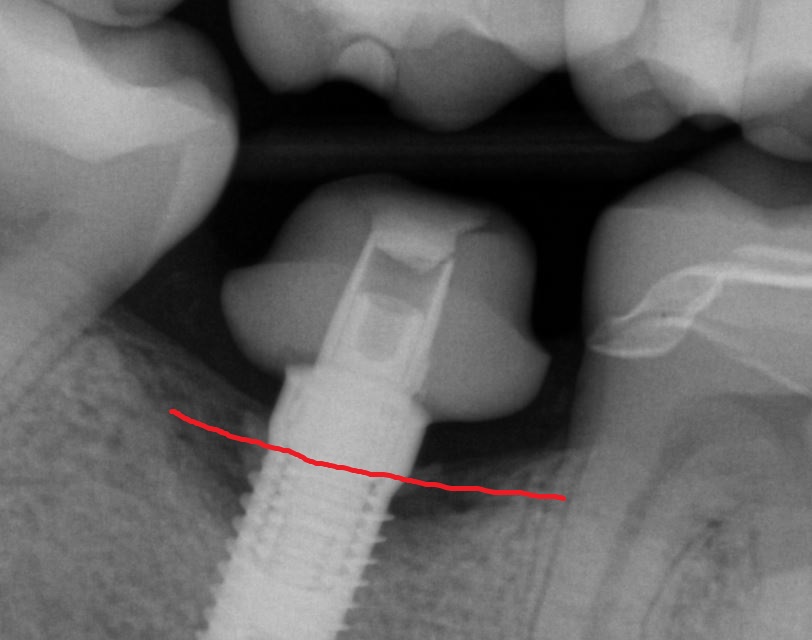

This implant was initially placed at the crest of the ridge in 2012. its placement did not allow proper emergence profile and subsequently lost bone around the head of the implant by 2015. The lack of blood flow to the crest of the bone at the cortical plate certainly could have contributed to its demise. By 2015, the bacteria trap forced a new restoration to be placed which also ultimately lead to chronic inflammation due to improper contours. The implant itself was well integrated and the decision was made to remove the top 3-5 mm of the implant and treat it as a cast post and core.

Post op x-rays to verify seat and no excess resin after flap was raised to clinically visualize that there is no excess cement